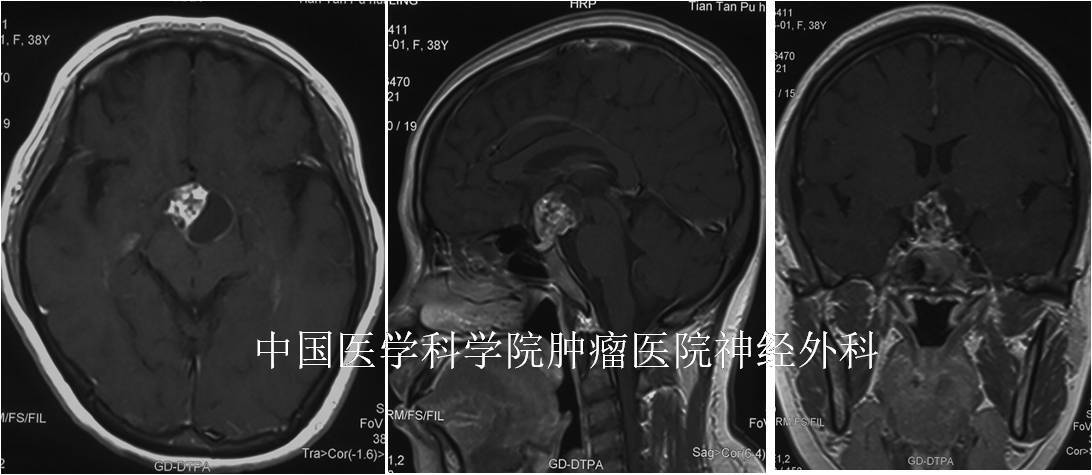

摘要:因“月經(jīng)不規(guī)律8月,頭痛半年”就醫(yī)的中年女性,檢查后發(fā)現(xiàn)是顱咽管瘤?;颊弋?dāng)?shù)責(zé)o法進(jìn)行內(nèi)鏡經(jīng)鼻蝶手術(shù),患者冒著當(dāng)時(shí)北京疫情風(fēng)險(xiǎn)、毅然來(lái)京隔離治療。幸而,我們通過(guò)經(jīng)鼻蝶內(nèi)鏡手術(shù)成功切除了腫瘤,緩解了患者頭痛、保護(hù)了患者的視力,內(nèi)分泌功能保護(hù)良好。在此提醒大家:平時(shí)有頭痛、頭暈、視力下降、看東西重影、視野范圍變化、內(nèi)分泌功能異常等問(wèn)題,一定要到專科就診評(píng)估、排除相關(guān)疾病風(fēng)險(xiǎn),不要盲目對(duì)癥處理,延誤病情?!净拘畔ⅰ颗?8歲【疾病類(lèi)型】鞍區(qū)-鞍上-三腦室顱咽管瘤【就診醫(yī)院】中國(guó)醫(yī)學(xué)科學(xué)院腫瘤醫(yī)院【就診時(shí)間】2020-5【治療方案】全麻下行內(nèi)鏡經(jīng)擴(kuò)大鼻蝶入路-鞍區(qū)-鞍上-三腦室顱咽管瘤切除+顱底重建術(shù)。【治療周期】住院13天,每半年門(mén)診隨訪。【治療效果】術(shù)后患者頭痛緩解,視力、內(nèi)分泌功能保護(hù)良好。一、初次面診???患者門(mén)診就診時(shí)一般情況還可以,告訴我自己主要是間斷頭痛?;颊?月前出現(xiàn)月經(jīng)不規(guī)律,當(dāng)?shù)蒯t(yī)院婦產(chǎn)科就診,對(duì)癥處理、效果。半年前無(wú)明顯誘因出現(xiàn)發(fā)作性頭痛不適,無(wú)惡心、嘔吐、抽搐等;當(dāng)?shù)蒯t(yī)院行頭顱MRI:提示鞍區(qū)-鞍上腫瘤。發(fā)病至今,無(wú)視力下降、肢體活動(dòng)障礙、感覺(jué)異常;精神可,睡眠可,飲食可,二便可,體重?zé)o明顯改變。???患者家屬剛確診時(shí)曾在網(wǎng)上咨詢我,我通過(guò)閱片考慮是顱咽管瘤、認(rèn)為可以經(jīng)鼻蝶手術(shù)切除;因疫情原因,建議在本省治療。但患者在本省多家醫(yī)院就診咨詢、都表示無(wú)法進(jìn)行鼻內(nèi)鏡手術(shù)。后來(lái)北京疫情稍緩解,患者決定來(lái)京隔離、到我院治療。二、治療經(jīng)過(guò)患者來(lái)院時(shí)一般情況可,查體:神清語(yǔ)利,高級(jí)智能檢查正常。嗅覺(jué)粗測(cè)正常。雙眼視力粗測(cè)正常,視野粗測(cè)正常。雙瞳孔等大等圓,直徑4mm,光反射存在。雙側(cè)額紋對(duì)稱,雙眼閉目有力。鼻唇溝對(duì)稱正常,口角無(wú)偏斜。雙耳聽(tīng)力粗測(cè)正常。伸舌居中。四肢肌力、肌張力正常。軀干及四肢感覺(jué)異常。病理征(-)。為了進(jìn)一步明確診斷,完善了頭顱MRI、CT,結(jié)果提示:鞍區(qū)-鞍上-三腦室腫瘤,形態(tài)欠規(guī)則、邊界尚清,呈混雜等長(zhǎng)T1信號(hào)、混雜長(zhǎng)T2信號(hào),呈明顯囊實(shí)性,左后上部囊變明顯;增強(qiáng)后實(shí)性腫瘤呈明顯斑點(diǎn)狀強(qiáng)化,周?chē)冶谳p度強(qiáng)化;鞍底可見(jiàn)正常垂體組織、形態(tài)完整;垂體柄顯示不清;腫瘤向前上突入終板池,視交叉受壓上抬;向后上突入三腦室內(nèi);后方突入腳尖窩、與基底動(dòng)脈尖部關(guān)系密切;側(cè)方與頸內(nèi)動(dòng)脈顱內(nèi)段關(guān)系密切。腫瘤CT上呈混雜密度,大部呈低密度,腫瘤周邊可見(jiàn)點(diǎn)、片狀高密度鈣化灶。根據(jù)病史和臨床癥狀,并結(jié)合頭顱MRI的結(jié)果,初步診斷為鞍區(qū)-鞍上-三腦室顱咽管瘤。入院后,醫(yī)護(hù)人員對(duì)患者的心理進(jìn)行疏導(dǎo),獲得患者及其家屬的同意后,完善垂體激素、皮質(zhì)醇、血常規(guī)、生化、凝血、心電圖等常規(guī)術(shù)前檢查,未見(jiàn)明顯異常,排除手術(shù)禁忌癥?;颊唢B咽管瘤、突入鞍上-三腦室,可能危及患者視力和內(nèi)分泌功能,因此建議患者進(jìn)行手術(shù)、切除腫瘤,保護(hù)視力和內(nèi)分泌功能。術(shù)前向患者和家屬充分講解了手術(shù)的必要性和手術(shù)相關(guān)的風(fēng)險(xiǎn),征得了患者和家屬的同意和配合。在充分完善術(shù)前相關(guān)準(zhǔn)備工作后,在全麻下進(jìn)行了內(nèi)鏡經(jīng)擴(kuò)大鼻蝶入路-鞍區(qū)-鞍上-三腦室顱咽管瘤切除+顱底重建術(shù),手術(shù)順利,耗時(shí)5小時(shí)?;颊咔逍押蟀卜挡》俊Pg(shù)后腫瘤標(biāo)本送病理學(xué)檢查。術(shù)后給予患者頭孢呋辛預(yù)防性抗感染治療48小時(shí),并給予止血、止吐、保護(hù)胃粘膜、補(bǔ)液支持等對(duì)癥冶療,患者恢復(fù)順利。三、治療效果術(shù)后病人恢復(fù)良好,體溫正常,術(shù)后第2天恢復(fù)流食,第5天下床活動(dòng)。術(shù)后前3天曾有一過(guò)性尿崩。查體:神清語(yǔ)利,高級(jí)智能檢查正常。雙眼視力、視野粗測(cè)正常。雙瞳孔等大等圓,直徑4mm,光反射存在。雙側(cè)額紋對(duì)稱,雙眼閉目有力。鼻唇溝對(duì)稱正常,口角無(wú)偏斜。雙耳聽(tīng)力粗測(cè)正常。伸舌居中。四肢肌力、肌張力正常。軀干及四肢感覺(jué)異常。病理征(-)。頸部柔軟、無(wú)強(qiáng)直。術(shù)后第7天拔除鼻腔碘仿紗條,鼻腔干燥,無(wú)異常滲出。術(shù)后第9天復(fù)查頭顱MRI:提示腫瘤切除徹底,顱底重建良好。術(shù)后第10天順利出院。病理結(jié)果回報(bào):顱咽管瘤。四、注意事項(xiàng)1、手術(shù)前積極配合醫(yī)生調(diào)整身體狀況,保證充足的睡眠。2、術(shù)前配合醫(yī)生完善頭顱CT、MRI等輔助檢查,以明確病變部位和范圍,制定合理的手術(shù)方案。3、術(shù)后做好鼻腔手術(shù)通道的管理,保持大便通暢、避免咳嗽打噴嚏,防止腦脊液漏。4、術(shù)后嚴(yán)格根據(jù)醫(yī)囑用藥,降低術(shù)后發(fā)生顱內(nèi)感染等并發(fā)癥的風(fēng)險(xiǎn)。5、出院后注意休息,注意清淡飲食,均衡營(yíng)養(yǎng),避免過(guò)度用眼,保證充足的睡眠。6、出院后注意保暖、保持大便通暢、心情舒暢,避免感冒咳嗽、搬動(dòng)重物、用力大便等動(dòng)作,防止腦脊液漏發(fā)生。7、出院后,如有發(fā)熱、頭痛、惡心、嘔吐等不適癥狀,及時(shí)就近就診。8、3個(gè)月后回院復(fù)查頭顱MRI、垂體激素和皮質(zhì)醇等。五、個(gè)人感悟???顱咽管瘤,是一種較為棘手的鞍區(qū)-鞍上腫瘤,以往都需要開(kāi)顱手術(shù)切除。近20年來(lái),隨著顱底內(nèi)鏡技術(shù)的發(fā)展,內(nèi)鏡經(jīng)鼻蝶手術(shù)逐漸成為顱咽管瘤的主流手術(shù)方式,多數(shù)顱咽管瘤都可以在內(nèi)鏡下經(jīng)鼻蝶入路切除。內(nèi)鏡經(jīng)鼻蝶入路從腹側(cè)切除腫瘤,避免了腦組織分離和牽拉,能夠更好的保護(hù)腫瘤上方和側(cè)方的神經(jīng)和血管;更早的發(fā)現(xiàn)和保護(hù)垂體柄,從而更好的保護(hù)垂體功能;內(nèi)鏡手術(shù)的抵近觀察、繞角觀察和良好的照明優(yōu)勢(shì)使得顱咽管瘤的手術(shù)全切率、垂體功能保護(hù)水平都有所提高。內(nèi)鏡經(jīng)鼻蝶入路切除顱咽管瘤,術(shù)中形成高流量腦脊液漏,務(wù)必進(jìn)行良好的多層顱底重建,防止術(shù)后腦脊液鼻漏和顱內(nèi)感染。本例顱咽管瘤患者有癥狀的時(shí)間不長(zhǎng)、但腫瘤生長(zhǎng)期應(yīng)該很長(zhǎng)了,這也符合此類(lèi)良性腫瘤的發(fā)病特點(diǎn)。患者內(nèi)分泌功能的損害已經(jīng)比較明顯了、但視神經(jīng)功能尚處于代償階段,因此及時(shí)手術(shù)切除腫瘤、保護(hù)視力、防止內(nèi)分泌功能的進(jìn)一步損害至關(guān)重要。幸而,經(jīng)過(guò)我們的精心手術(shù)后,患者的視力保護(hù)的很好、但內(nèi)分泌功能想完全恢復(fù)很困難。在此提醒大家:平時(shí)有頭痛、頭暈、視力下降、看東西重影、視野范圍變化、內(nèi)分泌功能異常等問(wèn)題,一定要到專科就診評(píng)估、排除相關(guān)疾病風(fēng)險(xiǎn),不要盲目對(duì)癥處理,延誤病情。